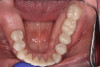

At a clinic treating patients in an underserved population, a 54-year-old female patient presented requesting extraction of all of her teeth and fabrication of dentures for her long-term restorations. The patient had a history of breast cancer, which had been treated with chemotherapy. She believed that full dentures would be an appropriate treatment option for her, owing to the poor state of her oral health and dentition and because she had limited financial resources and did not think that she could afford restoration of her teeth. The patient reported that she had experienced depression and alcohol abuse because of her cancer diagnosis, and that she had neglected her dental care during the course of her cancer treatment, resulting in generalized moderate-to-severe caries with moderate wear due to bruxism (Figure 1 through Figure 5). She also presented with significant staining of her remaining dentition due to the alcohol abuse.

Fig. 2